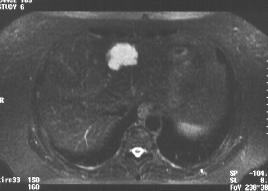

Ce patient est porteur d'un angiome typique connu, l'examen est réalisé pour rechercher d'éventuelles métastases hépatiques.

L'angiome est franchement hypo T1, et Hyper T2 sur les différentes séquences . Le fait que la lésion flash en turbo spin écho (TE 138) témoigne d'un contenu liquidien. Les contours polylobés sont très en faveur d'un angiome.